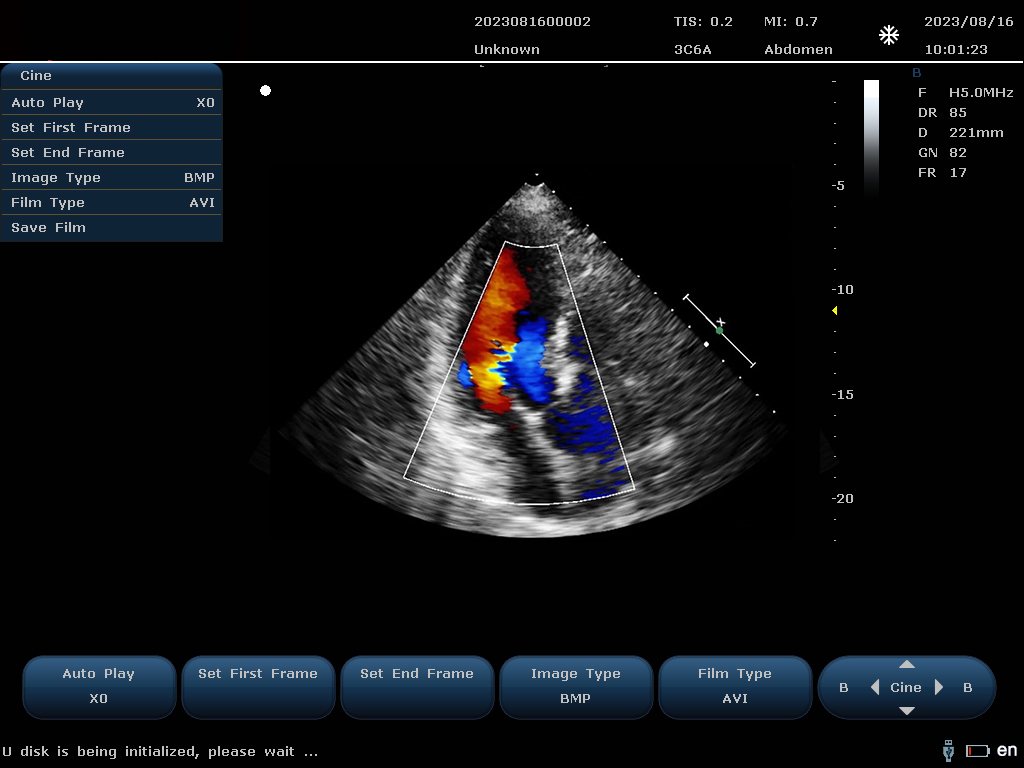

設(shè)備通過檢測這些頻移信號,并利用復雜的信號處理技術(shù),包括傅立葉變換等,分析血流的方向、速度和分布。彩色編碼后,血流信息被疊加在傳統(tǒng)的黑白超聲二維圖像上,形成彩色多普勒圖像,直觀顯示血流動態(tài)。

最終,這些信息轉(zhuǎn)化為圖像顯示在屏幕上,醫(yī)生可以根據(jù)圖像中血流的顏色(通常紅色代表血流朝向探頭,藍色代表遠離探頭)和亮度來判斷血流的性質(zhì)和異常情況,如血流速度增快可能指示狹窄,無血流區(qū)域可能意味著阻塞等。